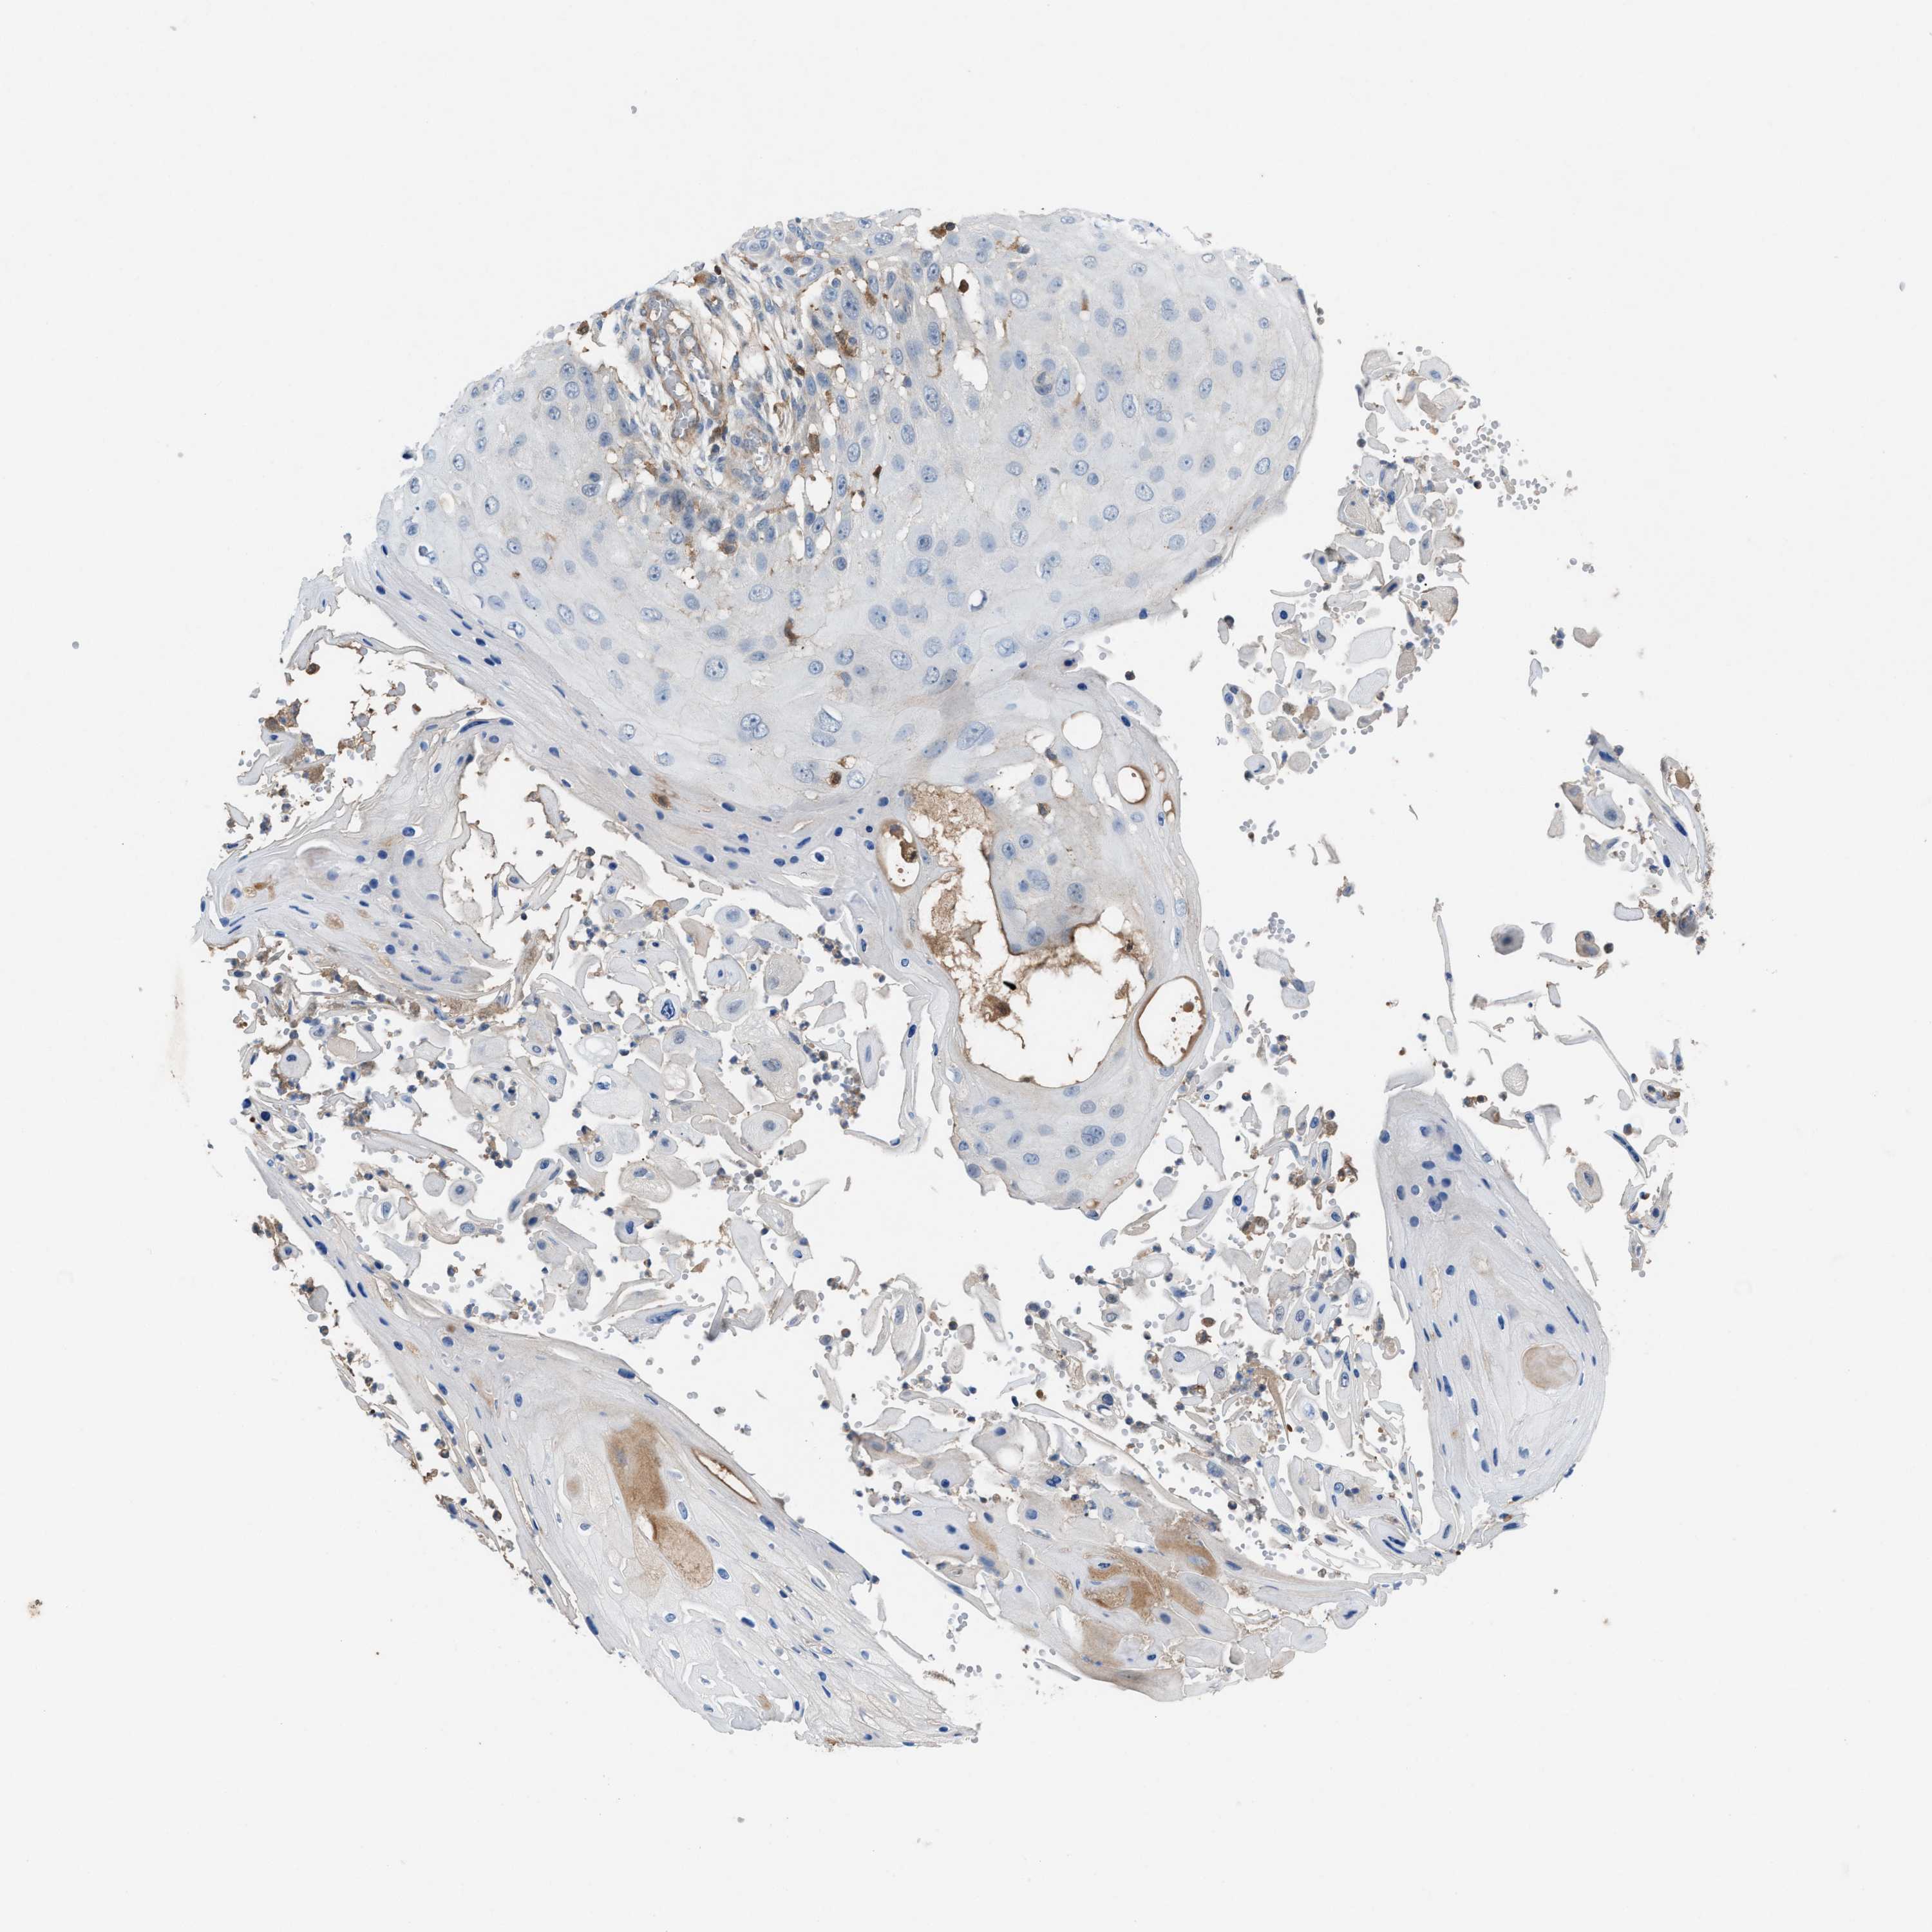

Basal cell and squamous cell cancer

SKIN CANCER - Protein expressioni

A mouse-over function shows sample information and annotation data. Click on an image to view it in a full screen mode. Samples can be filtered based on level of antibody staining by selecting one or several of the following categories: high, medium, low and not detected. The assay and annotation is described here.

Each image is clickable and will lead to virtual microscopy that enables deeper exploration of all samples and also displays staining intensity scores, fraction scores and subcellular localization as well as patient and tissue information for each sample.

Antibody HPA021545

Squamous cell carcinoma in situ, NOS

Squamous cell carcinoma, NOS

Squamous cell carcinoma, metastatic, NOS

Basal cell carcinoma